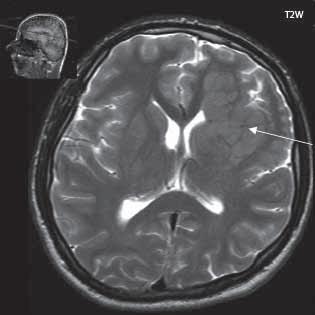

I 5 2 „Fyziologická“ ložiska zvýšeného signálu v T2W obrazu v bílé hmotě mozkové 187

Roztroušená skleróza (RS) 189